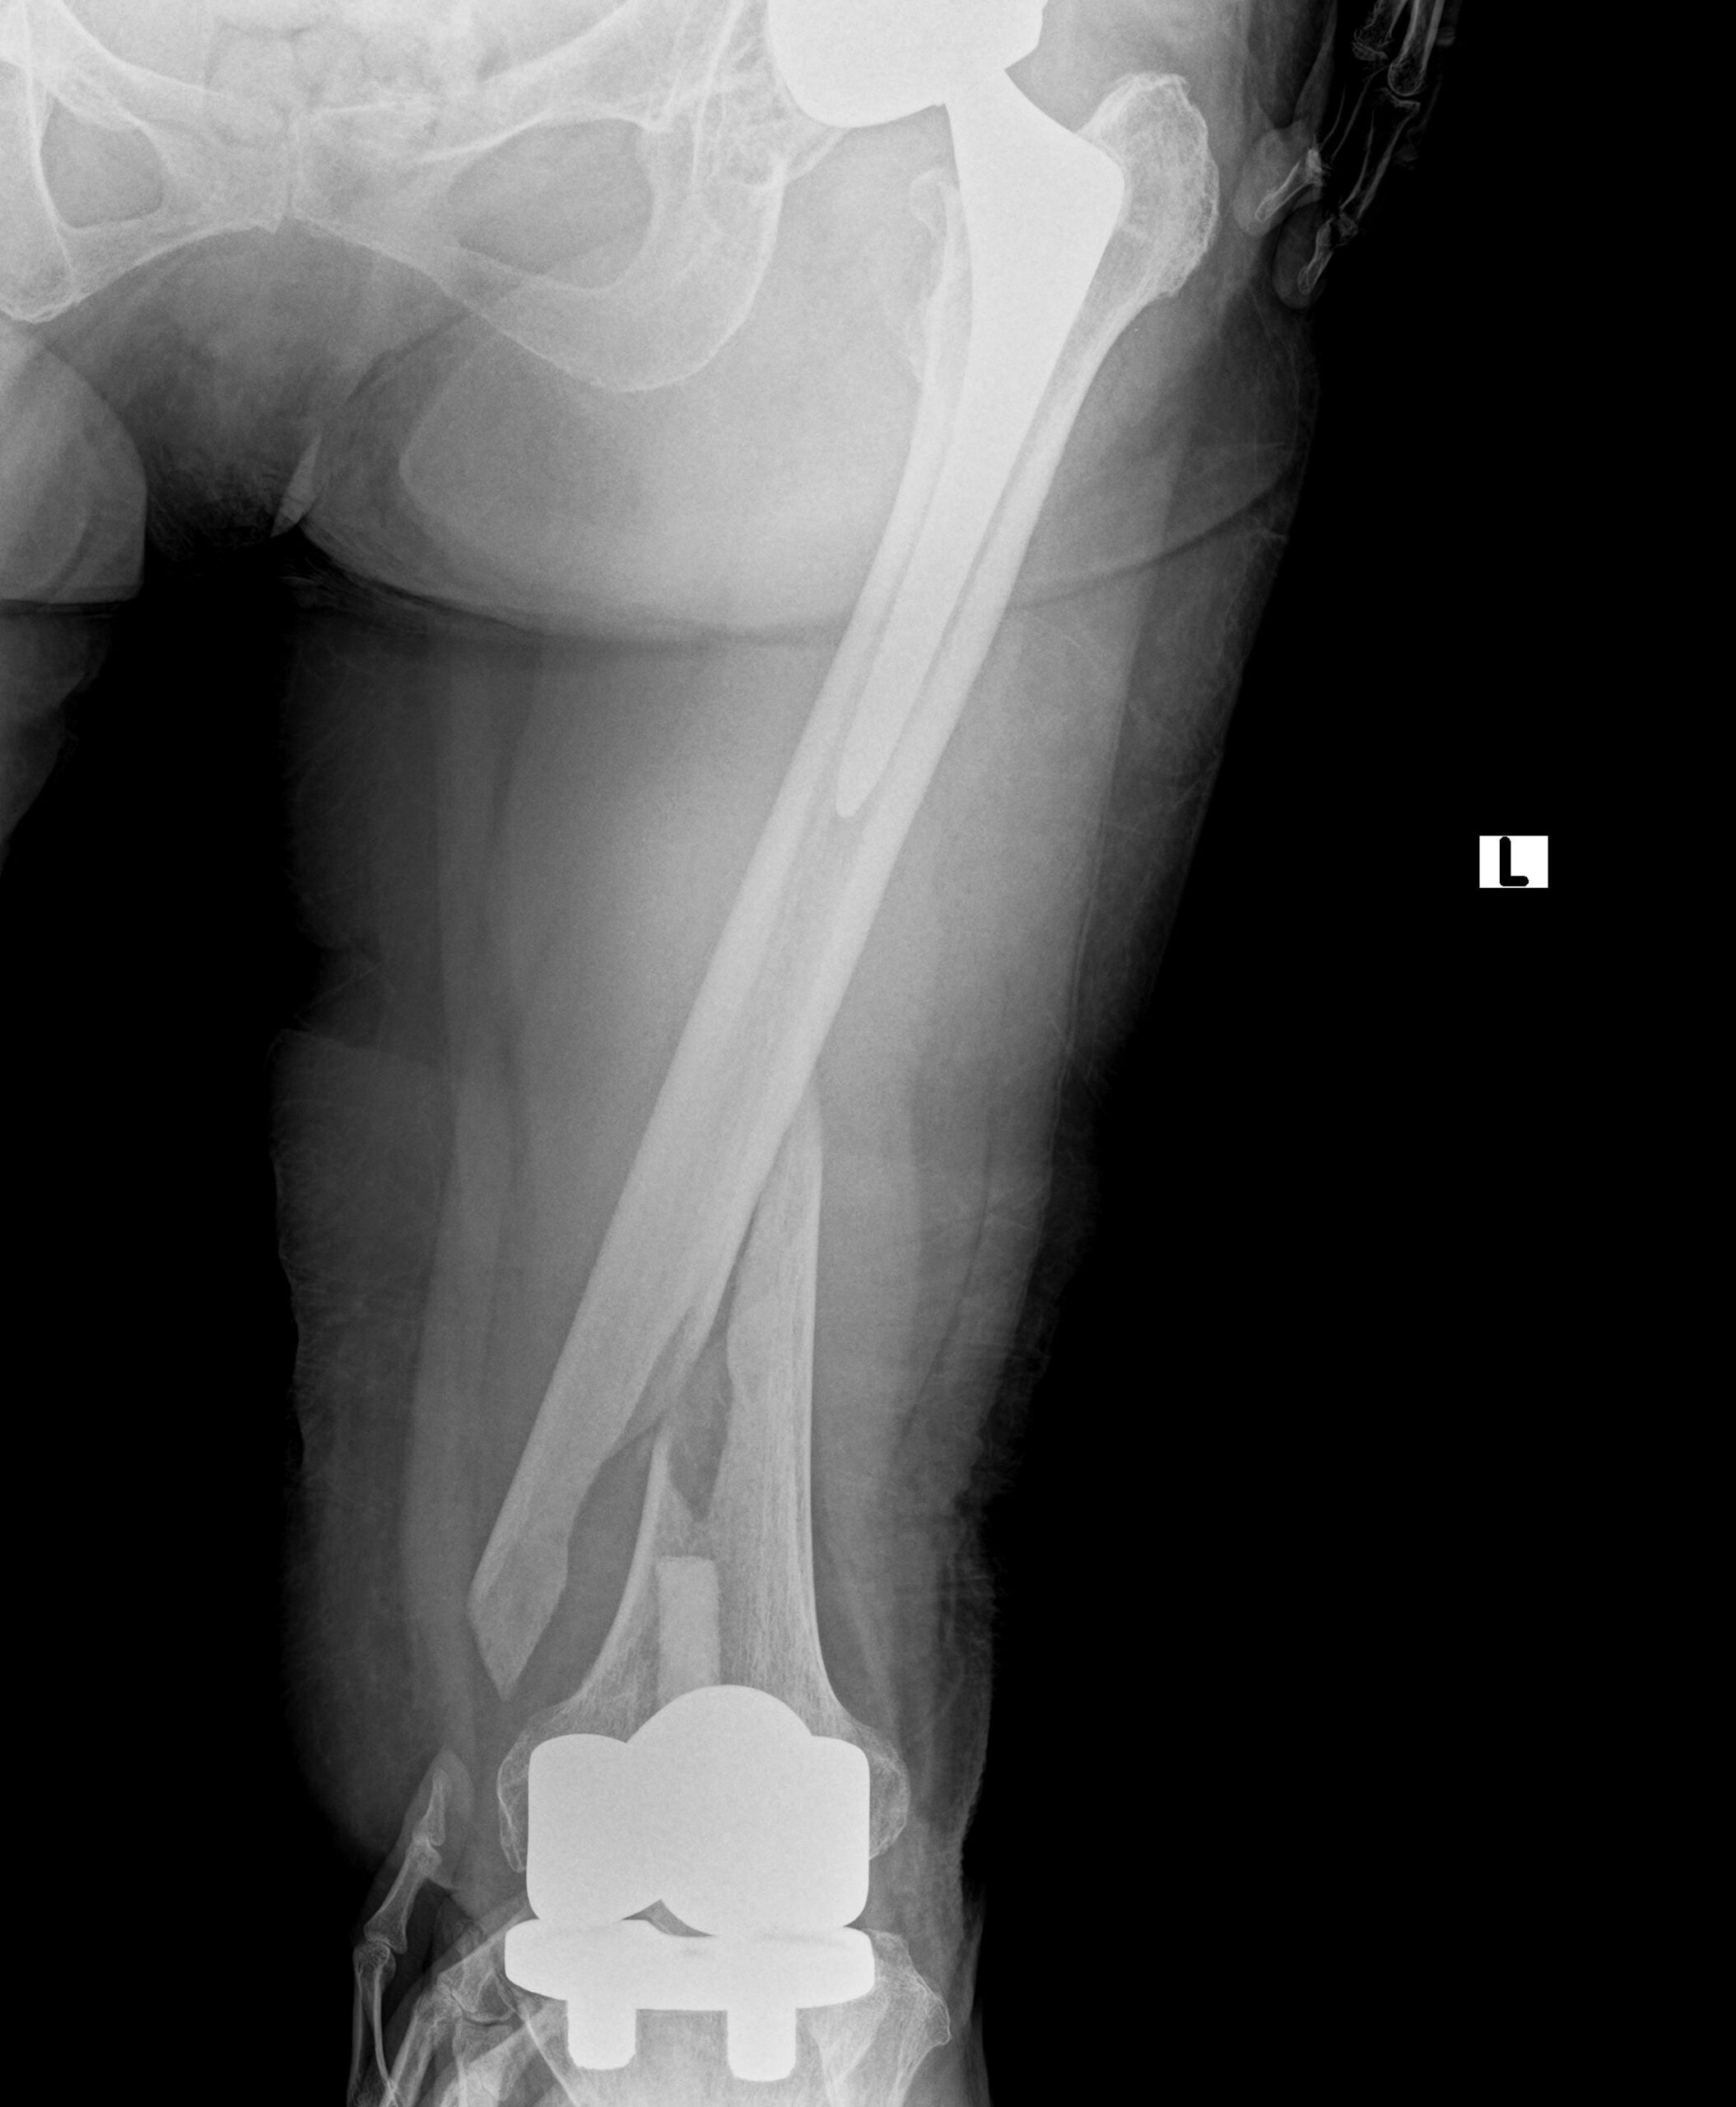

先日、左の人工股関節と左の人工膝関節手術を受けた70代の女性が、

転倒により左大腿骨骨折が生じたため手術治療を行いました。

人工股関節と人工膝関節の間で螺旋状に骨折しています。

通常であれば、膝関節を開けて逆行性髄内釘挿入手術を行います。

本来はそれほど難易度が高い手術ではありませんが、刺入部に膝人工関節、

固定すべき大腿骨近位に人工股関節があるため、挿入方向や髄内釘のサイズが限られ、

骨折整復が困難となります。